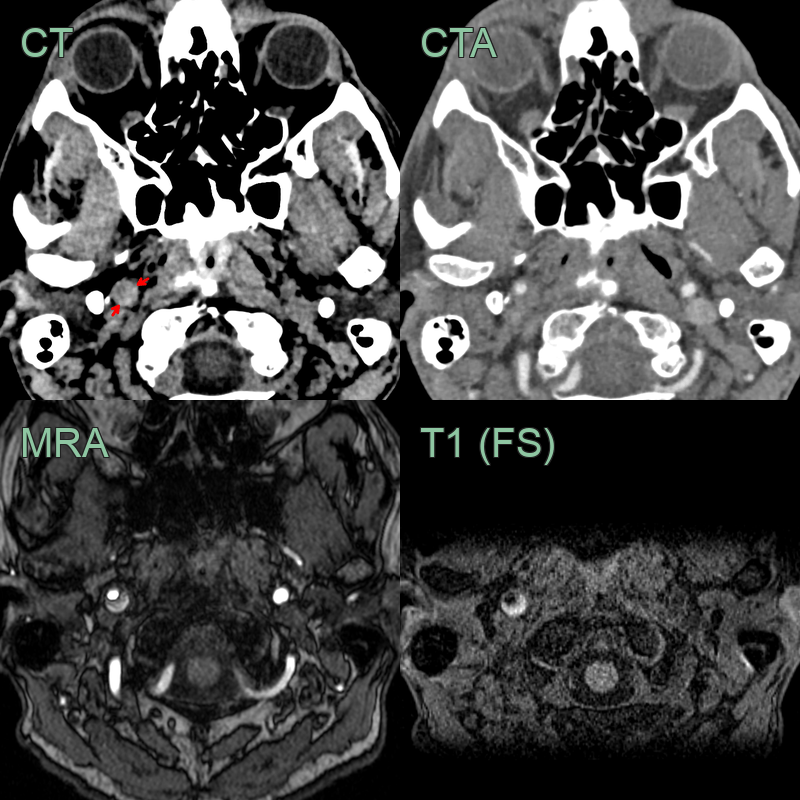

- 50-year-old patient presented with sudden onset right sided neck pain and a Horner's syndrome (blurred vision, right sided miosis and ptosis).

- The initial CT and CTA showed a hyperdense rim around an expanded right ICA below the skull base without a significant stenosis (yellow arrow).

- The T1-weighted imaging showed a T1-hyperintense rim around the ICA (red arrow).

- The mural thrombus also showed diffusion restriction (blue arrow) and blooming on SWI (not shown).